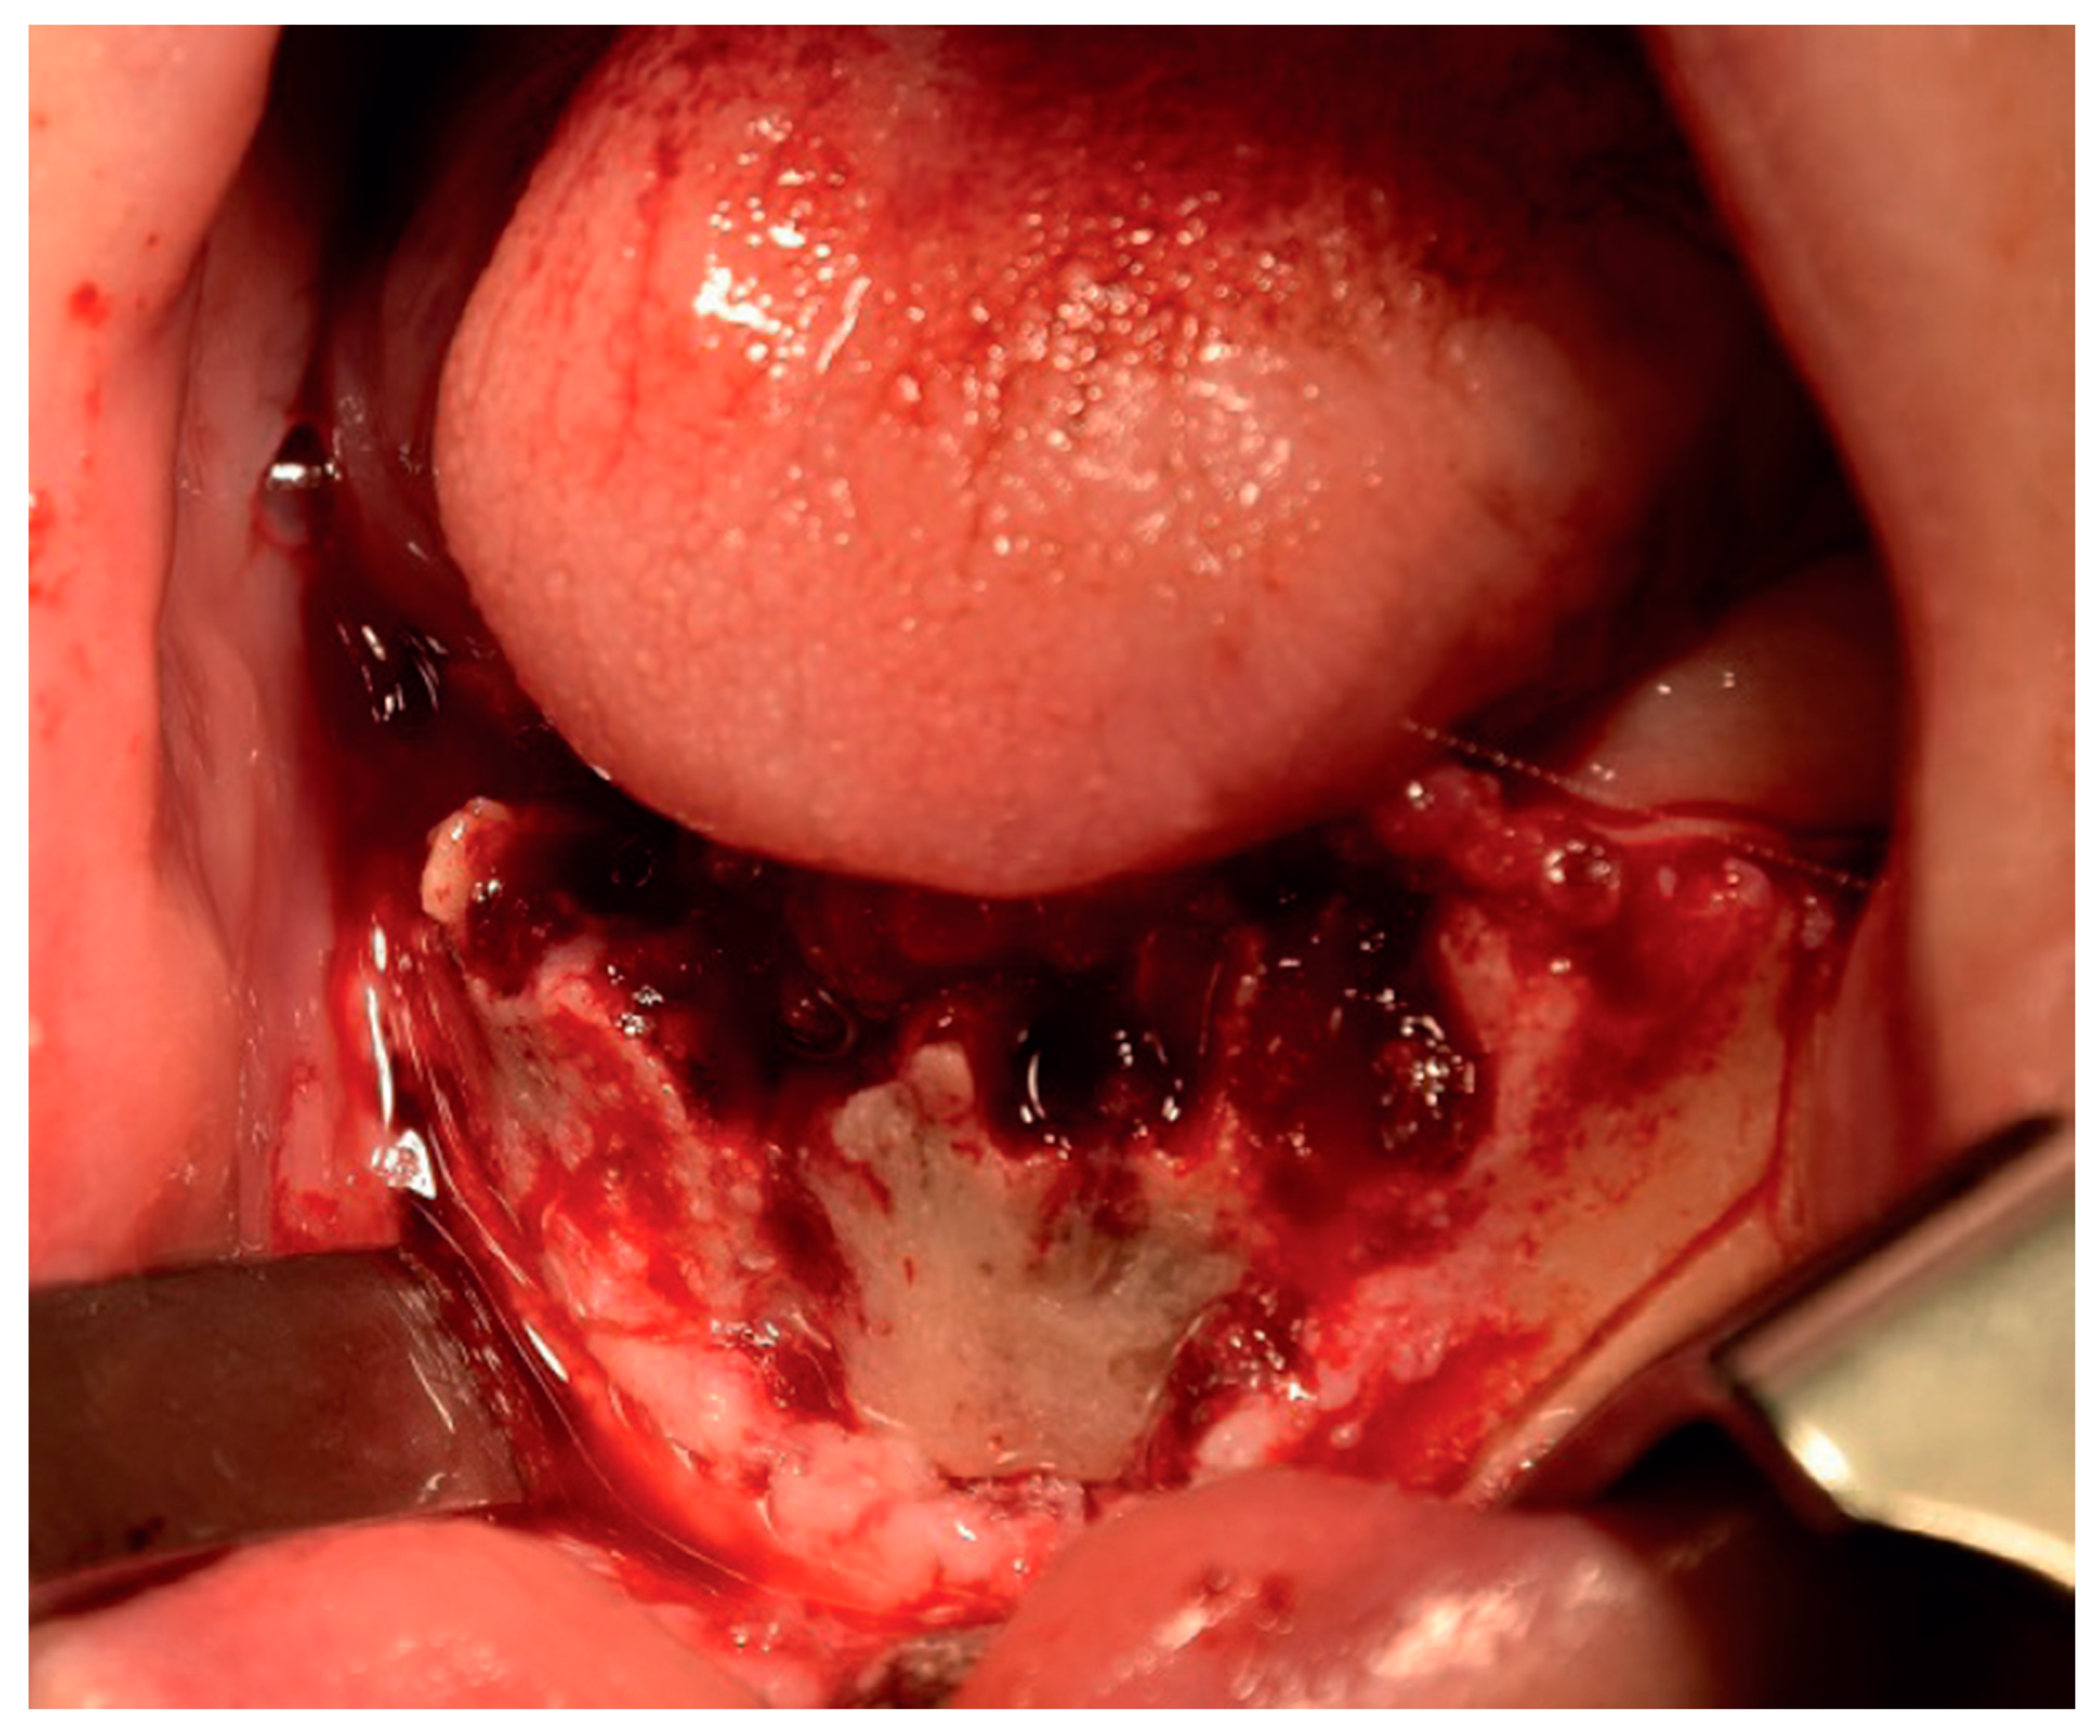

2.2. Clinical Findings

2.5. Therapeutic Intervention

3. Results